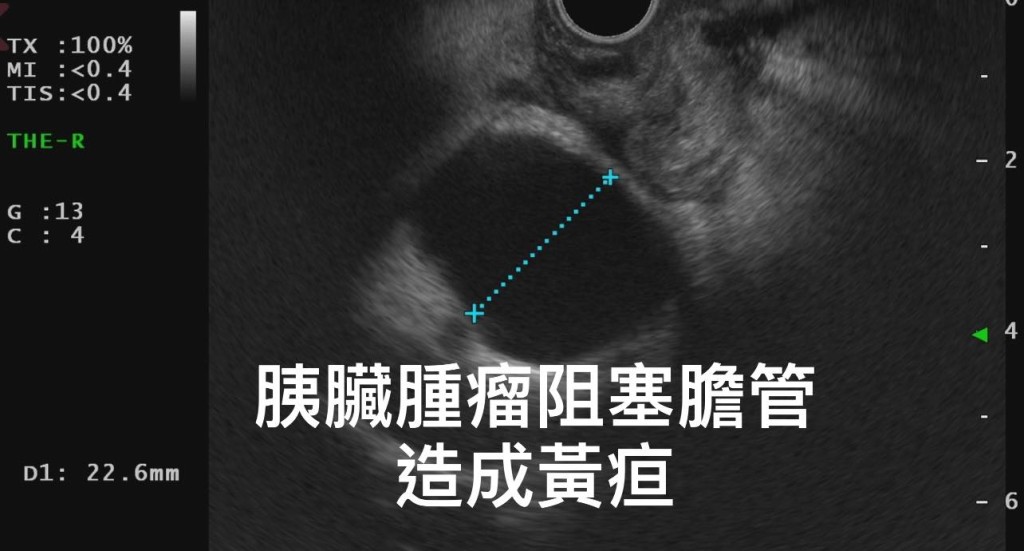

▲男子的胰脏肿瘤长达4cm(图片获胃肠肝胆科医生林相宏授权转载)

后来其家人上网查找原因,意识到该男子可能是胰脏出了问题,遂再度求医。 林相宏医生为该男子进行胰脏内窥镜超声波检查,赫然发现其胰脏头部有一颗近4cm大的肿瘤,并已导致胆汁和胰脏阻塞。 林医生发现,该男子小便颜色深似浓茶,是明显的黄疸状况。林相宏医生提醒,上述症状全是典型胰脏癌的表现。